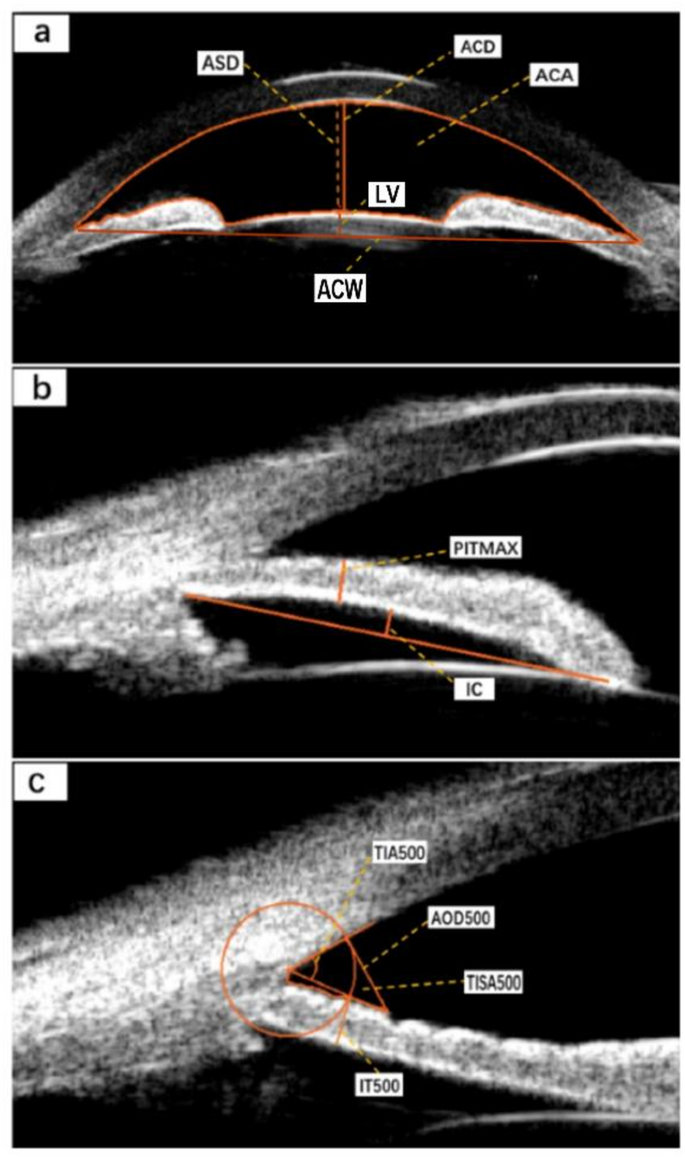

Based on the anterior segment parameter measurement methods reported in the literature9,10,11,12,13,14, clear UBM images were selected, and the measurement tools integrated into the software were used for precise measurements (Fig. 1). The parameters measured are as follows:

1. Anterior chamber depth (ACD): The distance from the inner surface of the cornea to the anterior surface of the lens.2. Anterior chamber width (ACW): The distance between the two scleral spurs.3. Anterior chamber area (ACA): The cross-sectional area enclosed by the inner surface of the cornea, the anterior chamber angle, the anterior surface of the iris, and the anterior surface of the lens. 4. Lens vault (LV): The vertical distance between the anterior surface of the lens and the horizontal line connecting the two scleral spurs.5. Relative position lens vault (RPLV): the ratio of lens vault height / (lens vault height and anterior chamber depth), reflecting the proportion of lens vault height in the anterior chamber. 6. Anterior segment depth (ASD): the sum of anterior chamber depth and lens vault height, reflecting the spatial size of the anterior chamber. 7. Angle opening distance at 500 μm, (AOD500): A straight line perpendicular to the inner surface of the cornea and intersecting with the anterior surface of the iris at 500 μm in front of the scleral spurs, the distance between the intersection of the line and the inner surface of the cornea and the anterior surface of the iris is defined as the angle opening distance. 8. Trabecular iris space area at 500 μm (TISA500): the area bounded anteriorly by AOD500, posteriorly by a line drawn from the scleral spur perpendicular to the plane of the inner scleral wall to the iris, superiorly by the inner corneoscleral wall, and inferiorly by the iris surface 9. Trabecular iris angle at 500 μm (TIA500): the angle between the inner surface of the trabecular meshwork and the anterior surface of the iris at 500 μm, with the scleral spurs as the apex. These three parameters directly reflect the contact between the iris and the trabeculae and are useful for understanding the degree of opening of the anterior chamber angle.10. Iris thickness at 500 μm (IT500): the thickness of the iris measured at 500 μm from the scleral spurs.11. Peripheral iris thickness maximum (PITMAX): the maximum thickness of peripheral iris. 12. Iris curvature (IC): the maximum vertical distance between the pupillary margin and the line connecting the iris root to the posterior surface of the iris, reflecting the degree of iris bulging.

(a) ACD: anterior chamber depth; ACA: anterior chamber area; ASD: anterior segment depth. ACW: anterior chamber width; LV: lens vault. (b) PITMAX: peripheral iris thickness maximum; IC: iris curvature. (c) AOD500: angle opening distance at 500 μm; TISA500: trabecular iris area at 500 μm; TIA500: trabecular iris angle at 500 μm; IT500: iris thickness at 500 μm.